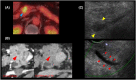

Pancreatic metastasis from lung adenocarcinoma

TTF-1 is a highly useful marker to assist in differentiating between pulmonary and nonpulmonary, nonthyroid adenocarcinomas. Our case shows that TTF-1 is highly useful in differentiating between pancreatic metastasis from lung adenocarcinoma and primary pancreatic cancer, especially when the clinical course and imaging findings are not helpful for differentiating them.